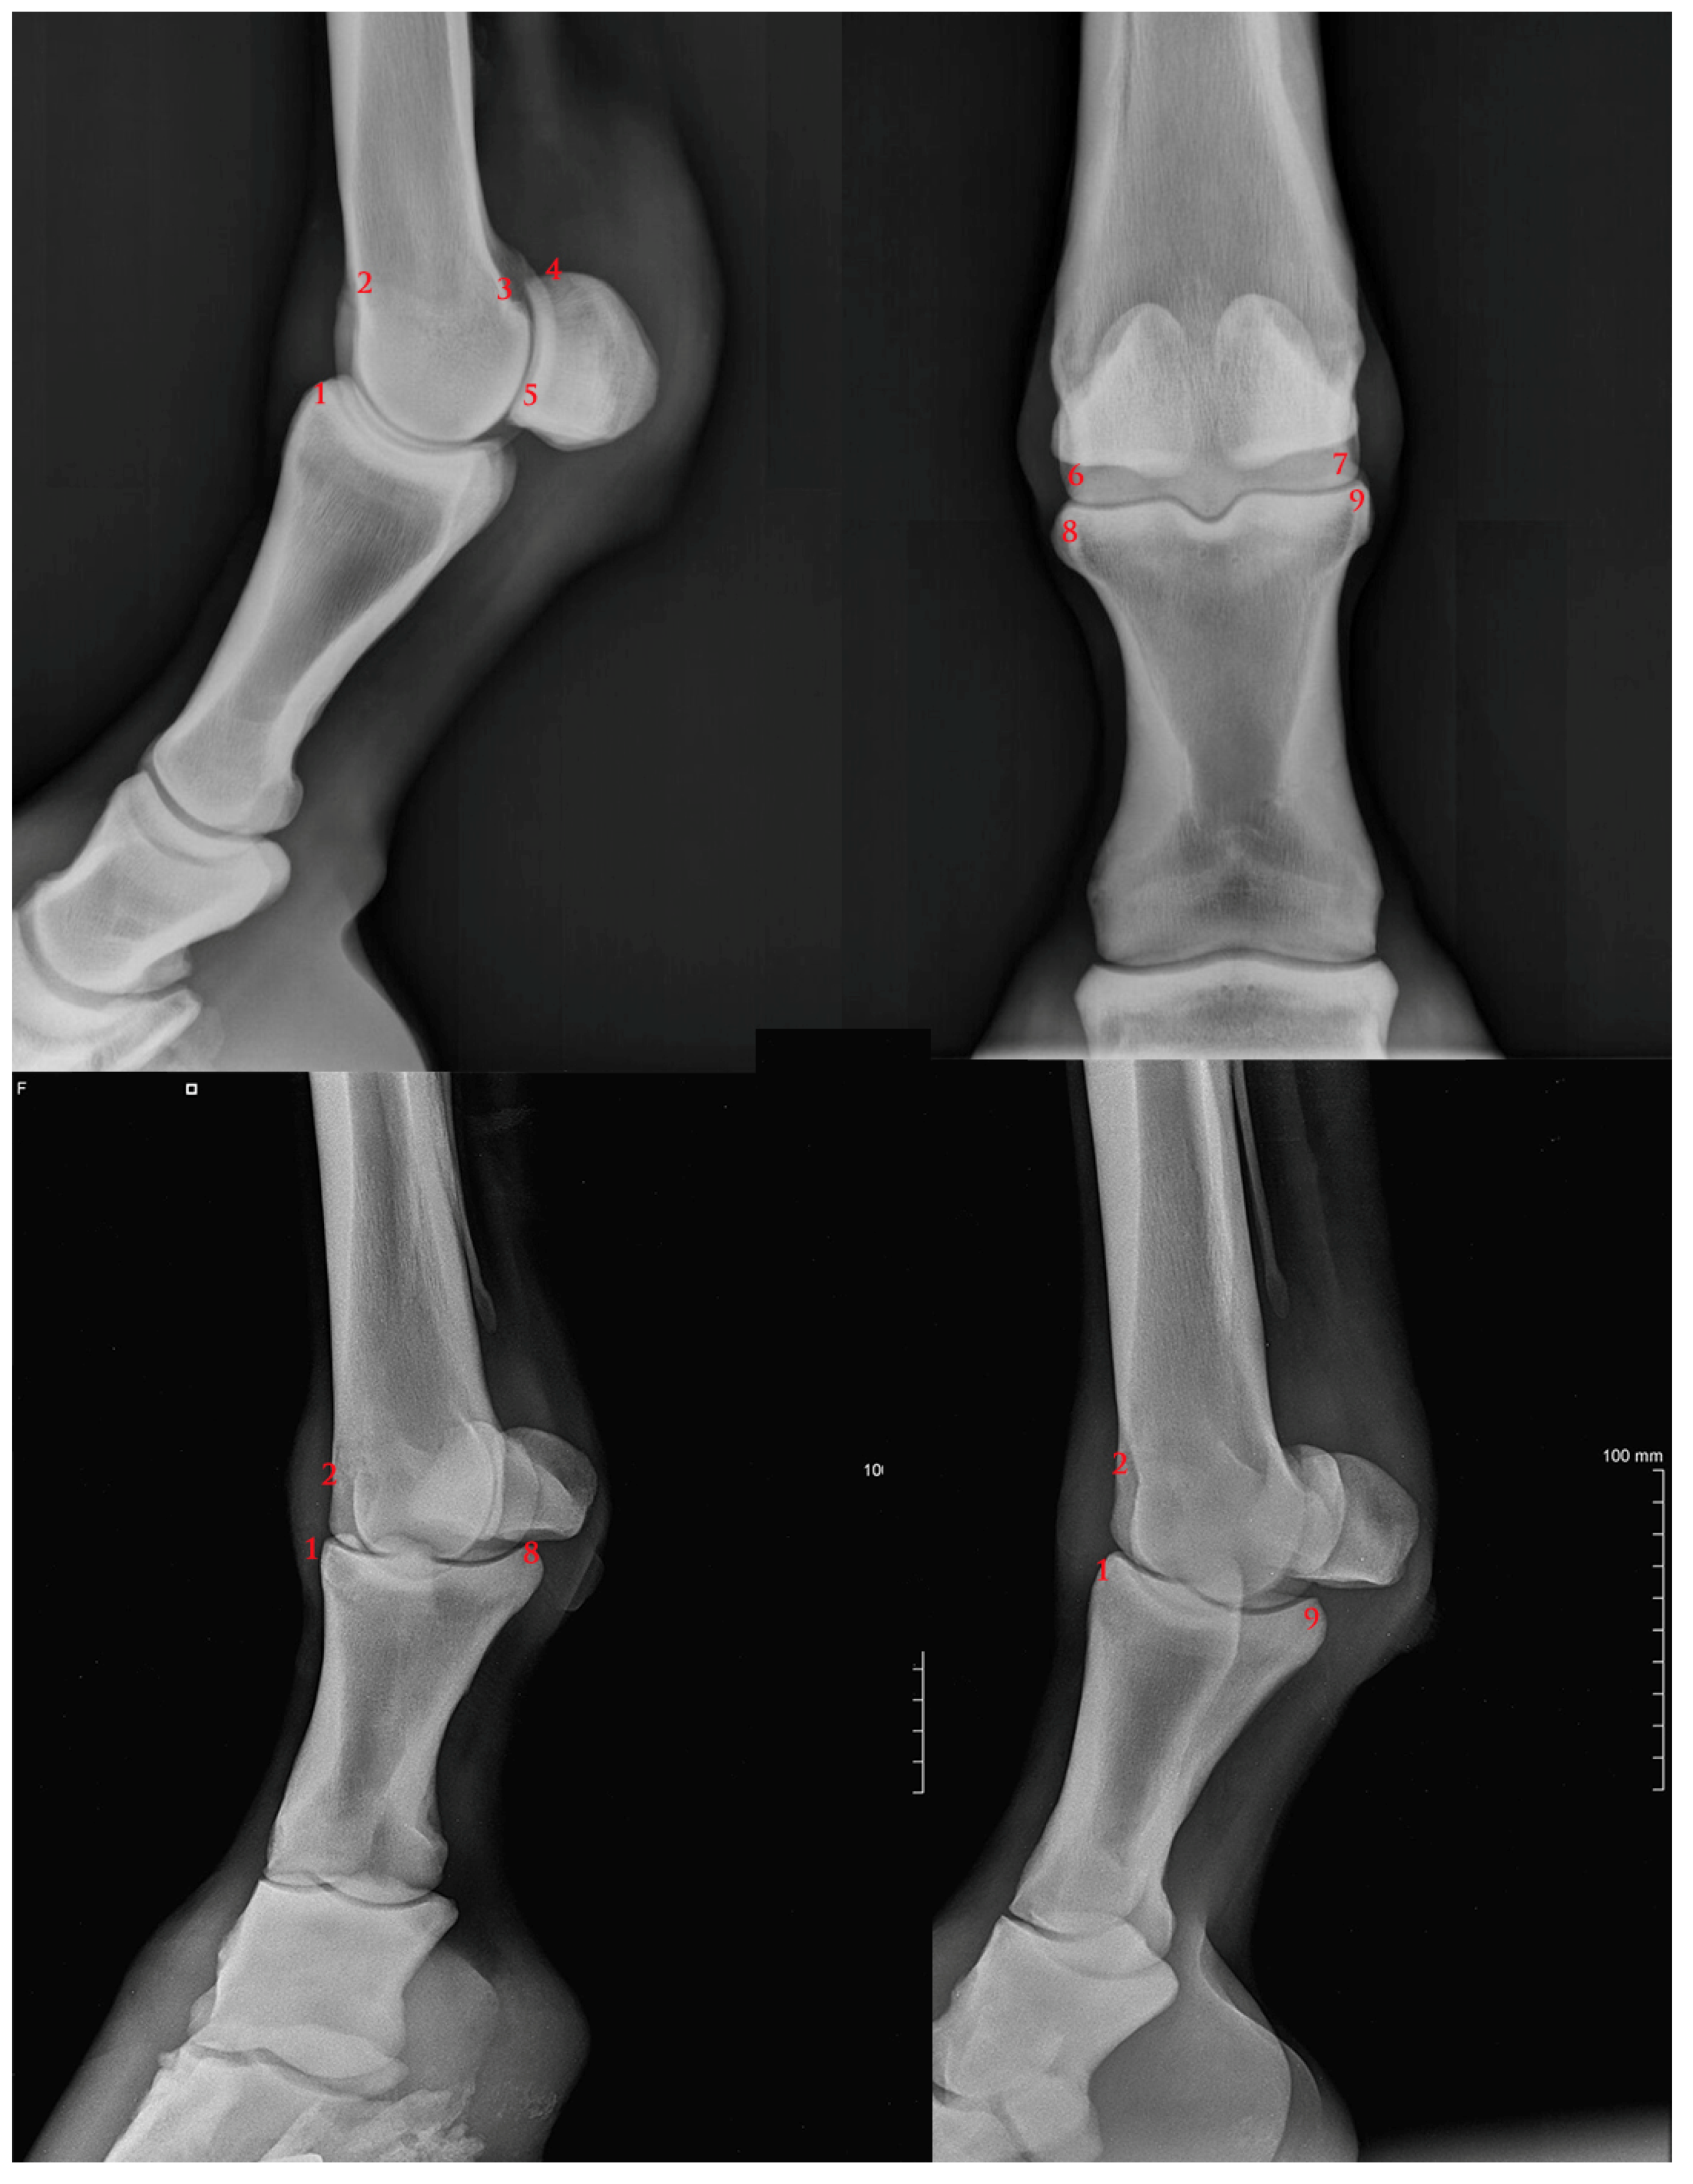

2.2. MCP Joint Osteophytes Scoring System